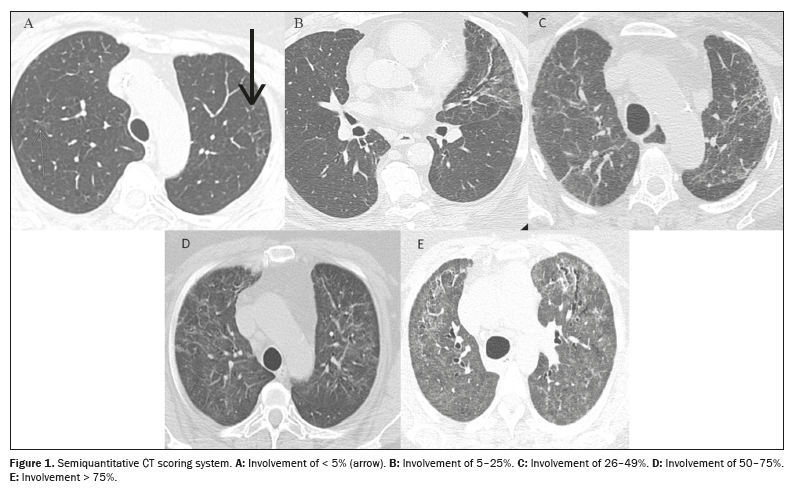

All of the images were evaluated by two thoracic radiologists with 8 and 12 years of experience, respectively, working independently; both were blinded to the clinical data and laboratory test results. Imaging characteristics were described as ground-glass opacities, reticular opacities, parenchymal bands, traction bronchiectasis/bronchiolectasis, and honeycombing, based on the standard glossary for thoracic imaging published by the Fleischner Society(15). Traction bronchiectasis/bronchiolectasis and honeycombing were further classified as fibrosis-like findings because they are associated with parenchymal distortion and irregular bronchopulmonary and pleuropulmonary interfaces(16). A semiquantitative scoring system(17) was used in order to assess the extent of lung involvement on chest CT scans. Each of the five lung lobes was visually scored on a scale of 0 to 5, with 0 indicating no involvement; 1 indicating involvement of < 5%; 2 indicating involvement of 5–25%; 3 indicating involvement of 26–49%; 4 indicating involvement of 50–75%; and 5 indicating involvement of > 75%. The total CT score was the sum of the individual lobar scores, therefore ranging from 0 (no involvement) to 25 (maximum involvement). Discrepancies between the two assessors regarding pulmonary findings were resolved by consensus. Figure 1 exemplifies the semiquantitative CT scoring system. The mean interobserver kappa value for qualitative variables was 0.72 [95% confidence interval (95% CI): 0.63–0.79] and the intraclass correlation coefficient for the extent of lung involvement on chest CT was 0.83 (95% CI: 0.70–0.91).